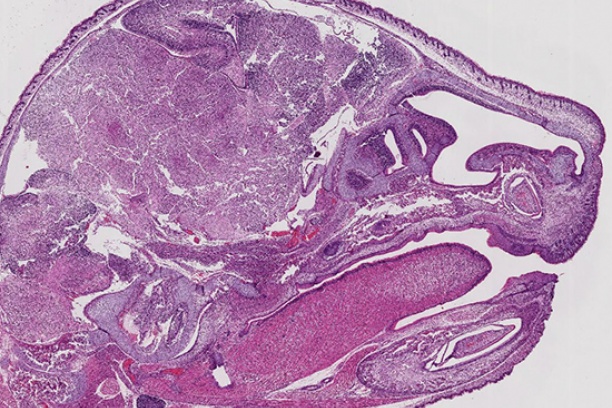

The Digital Histology Shared Resource provides large-scale digital archiving and quantitative analysis of histologic, immunohistochemical and immunofluorescence staining of tissue sections and tissue microarrays. Two Aperio Versa automated scanning microscopes, and Aperio AT2 and a Leica SCN400 Slide Scanner deliver solutions for high-resolution imaging in both bright field and fluorescence. All instruments have high-capacity robotic autoloading (200 slides for the Aperio Versa and Aperio AT2 and 384 slides for the Leica SCN400) making them ideal for large slide cohorts and tissue microarrays. The associated software packages provide complex algorithms for unbiased, automated image analysis and quantitation of immunostaining in both bright field and fluorescence. In addition, these systems can be utilized as a permanent high-resolution solution for those who need archiving of histologic material. The DHSR hosts a convenient, web-based digital slide-viewing environment (Digital Slide Archive) for the rapid retrieval, review, annotation and image acquisition of scanned material. This easy to use digital slide box allows researchers to share images among colleagues from any web browser while remaining in a digitally secure environment. Expert assistance is offered in planning experiments and processing data in a consistent, objective, and timely manner. The automated imaging and analysis performed in this core saves researchers and staff weeks of tedious work. An additional service offered by the DHSR is the creation of digital archives of critical and irreplaceable tissue samples, a benefit only feasible due to the automated high-resolution imaging of whole 25 mm x 75 mm microscope slides and 50 mm x 75 mm "double" slides.

The DHSR offers specialized microscopy assistance in addition to automated slide scanning and analysis, such as colony counting. The core is capable of high-resolution automated and semi-automated imaging and quantitation of a wide range of cell culture and tissue samples, from bacterial colonies to organoids. The GelCount• system by Oxford Optronix scans and counts mammalian cells, yeast or bacterial colonies in a wide variety of Petri dish and cell culture plate formats. This system is designed for the detection, counting and characterization of stained/adherent mammalian cell colonies or of unstained/non-adherent colonies in soft agar or collagen assays, but also works very well for yeast and bacterial colonies. The software is fully trainable and can be programmed to recognize specific colony features. Detailed information such as diameter, area, density, and nearest neighbor is provided, as well as high-resolution images.